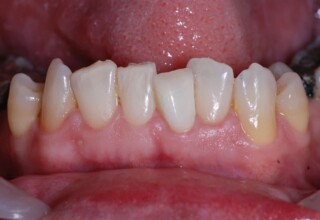

Οι όψεις πορσελάνης είναι ο καλύτερος τρόπος αντιμετώπισης αισθητικών προβλημάτων στην πρόσθια περιοχή του στόματος. Συνδυάζουν συντηρητική αφαίρεση οδοντικής ουσίας και πολύ υψηλή αισθητική απόδοση. Στο παρακάτω εκτεταμένο περιστατικό υπήρχαν: παλαιά σφραγίσματα, δυσχρωμίες, κακό σχήμα και μήκος δοντιών, κακή αναλογία δοντιών-ούλων. Έγινε προσεκτικός εργαστηριακός σχεδιασμός σε εκμαγεία απ’όπου προέκυψαν προσωρινές όψεις που τοποθετήθηκαν στο στόμα για δοκιμή και διορθώσεις. Όταν οριστικοποιήθηκαν οι μετατροπές, οι προσωρινές χρησιμοποιήθηκαν σαν οδηγός για τις μόνιμες. Οι πέντε μόνιμες όψεις πορσελάνης που κατασκευάστηκαν για τα πέντε πρόσθια δόντια της άνω απεκατέστησαν σχεδόν άψογα την αισθητική εμφάνιση της ασθενούς.